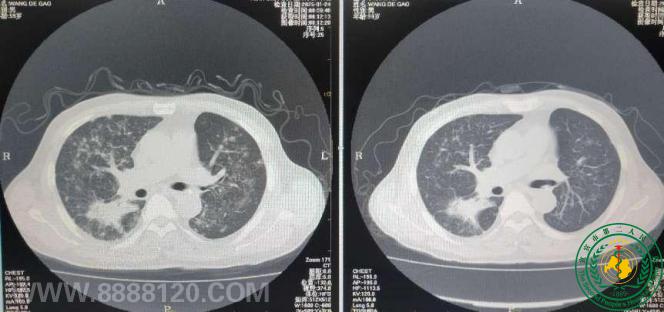

宜宾市第二人民医院 图文